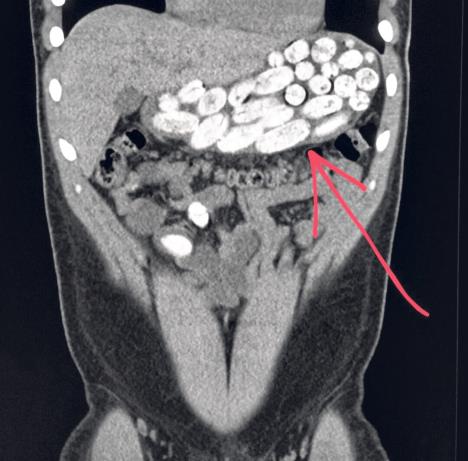

„Mule“ gutaju drogu u kesicama ili kapsulama, a izbace je kad dođu na odredište. Kod nekih je nađeno po nekoliko stotina paketića ili kapsula, a kod pojedinih žena droga je nađena u polnom organu. Oni za ovaj posao dobijaju po nekoliko hiljada evra po pošiljci.